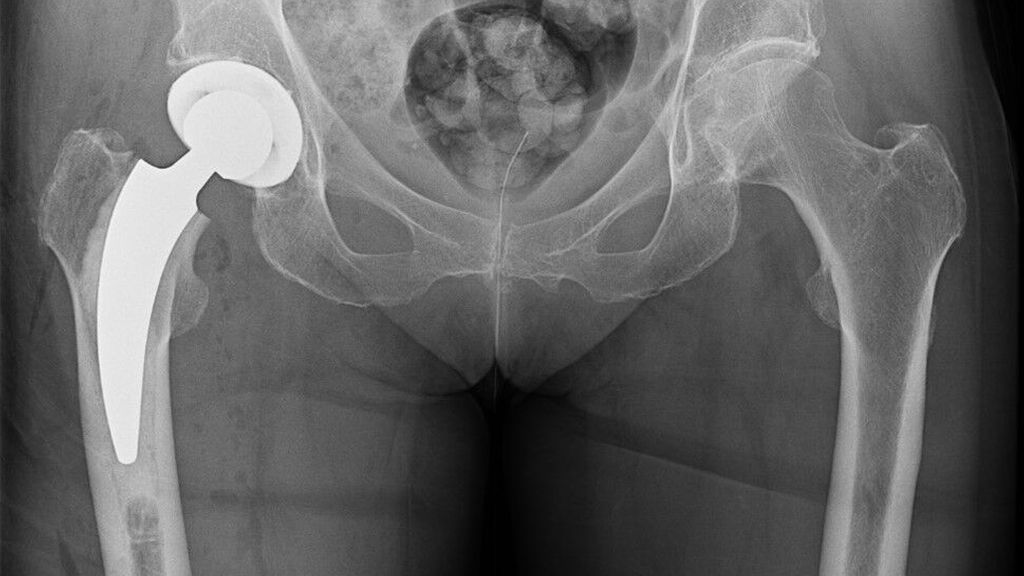

Operative Versorgung mit zementierter Kurzschaftprothese

Mit zunehmendem Alter steigt die Rate an dislozierten medialen Schenkelhalsfrakturen. Meistens wird ein zementfreier oder zementierter Langschaft verwendet, seit Längerem werden auch ...